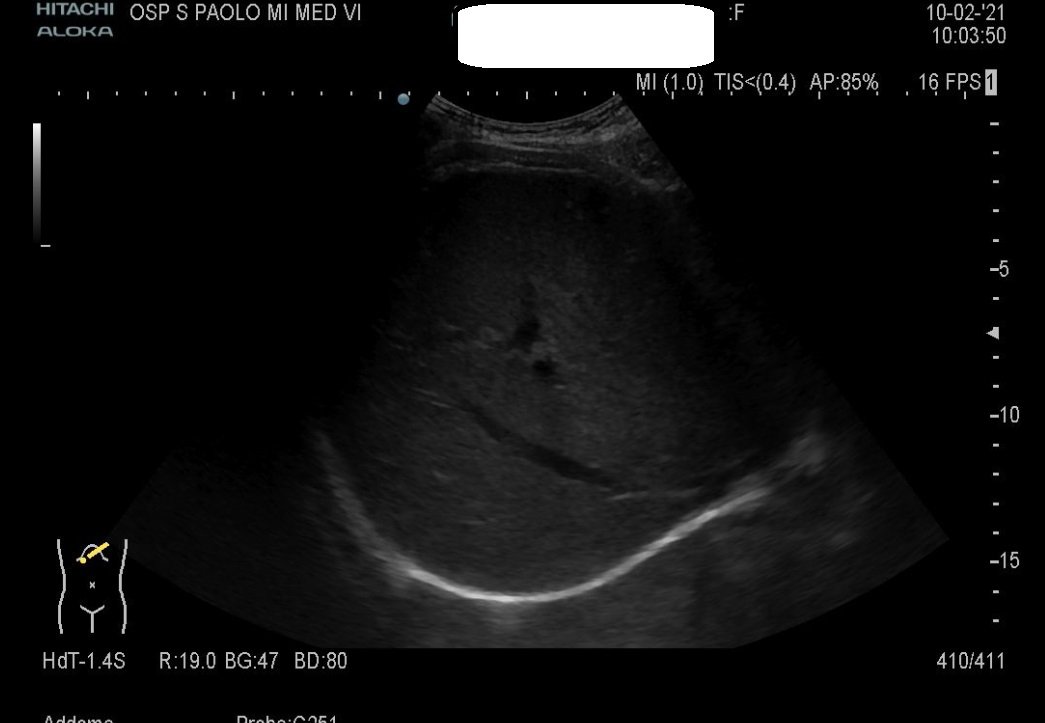

1) IVC is clearly dilated with absence of inspiratory collapse.

2) Dilated hepatic veins